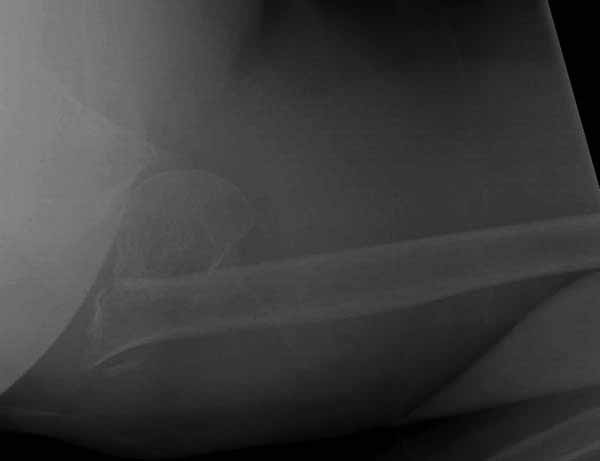

Здесь результат похожего случая, больная 87 лет, отягощенная сердечными делами и два года назад установка pacemaker и нескольких стентов. На третий день, сегодня утром сделали операцию. Послеоперационный псевдовывих связанный с релаксацией мышц и общим обезболиванием.